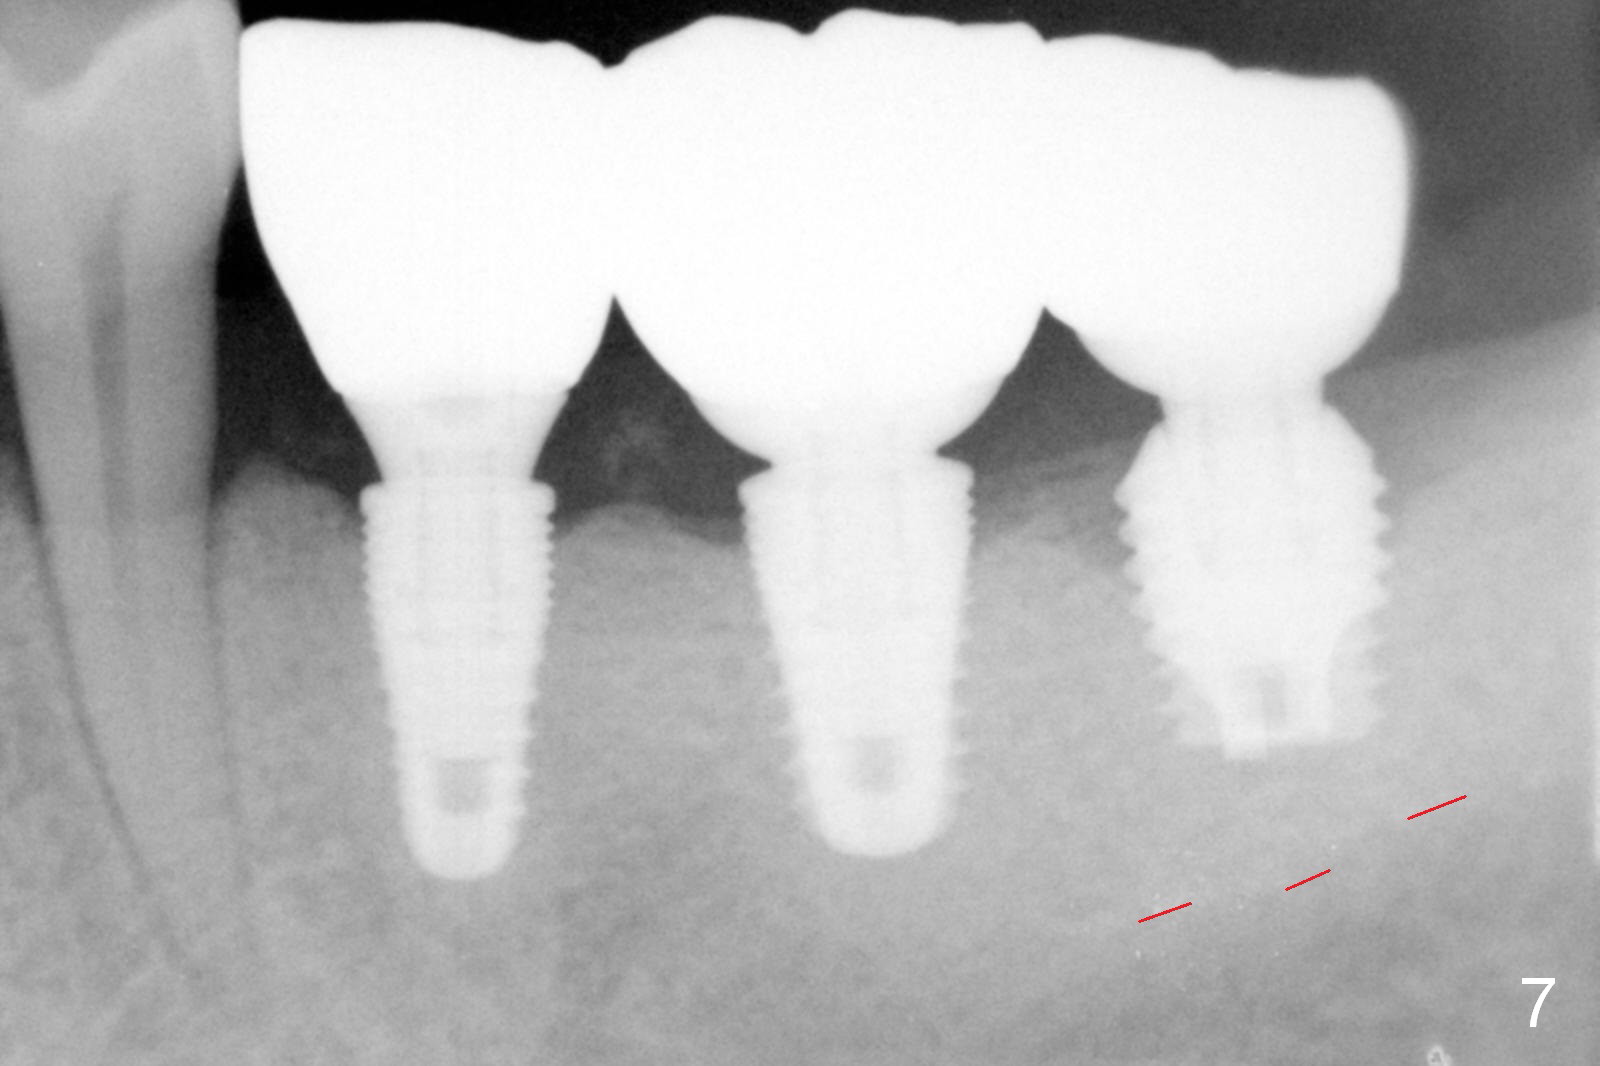

Five months post cementation, the patient returns because of loose abutment screw at #18. Bone resorption is noted (Fig.7 arrowheads). His oral hygiene is fair. He refuses implant at #2, saying that he dares not to chew on the left. When the screw became loose again 3 months later, he accepted the treatment. While he was returning to his home country, the lower right bridge was sectioned and the tooth #30 was removed. He is thinking of 2 implants at #29 and 30 (Fig.8). Bone loss appears not to get worse at #18-20 (Fig.9-11 (CBCT coronal sections, 2 years 7 months post cementation)). The implant at #19 is loose with a gap between the implant and the bone 3 years 5 months post cementation (Fig.12 *). SM implant does not last under stress (bruxism) and rigid implant/abutment connection.